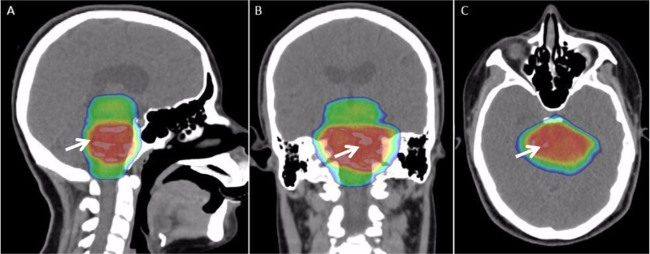

- w celach leczniczych i diagnostyce (radioterapia, medycyna molekularna);